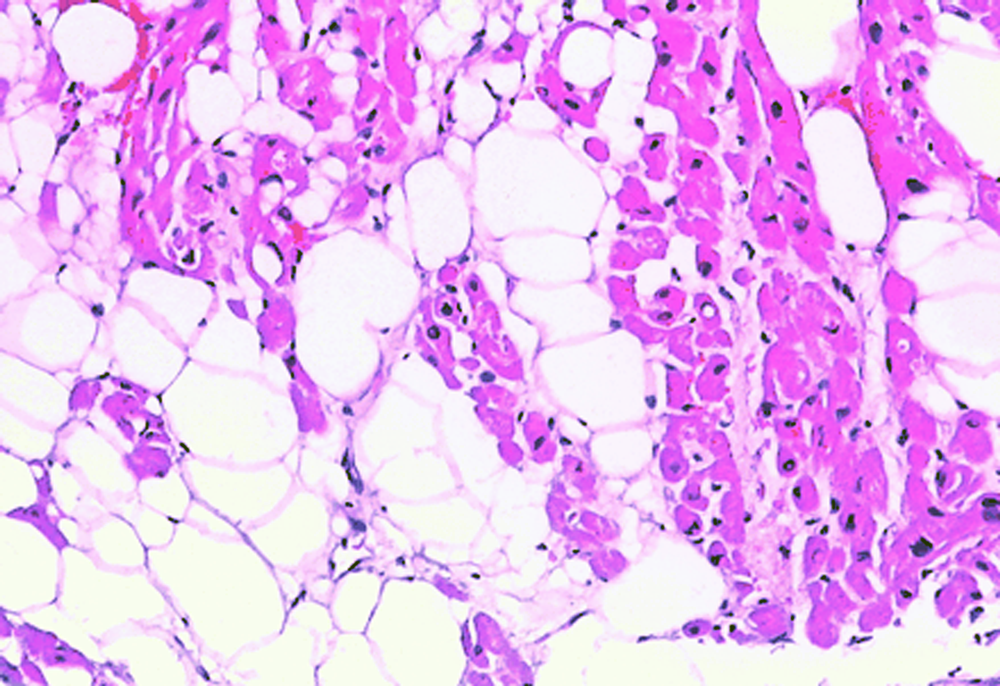

Sehen Sie nachfolgend einige Bilder, auf denen verschiedene Untersuchungsergebnisse gezeigt werden:

Fettige Degeneration der Herzmuskels. Das Fett erkennt man an den großen weißen Blasen zwischen den rot gefärbten Herzmuskelzellen. In diesem Fall ist sie Folge einer angeborenen Herzerkrankung (rechtsventrikuläre Dysplasie), die zu schweren Herzrhythmusstörungen führen kann.